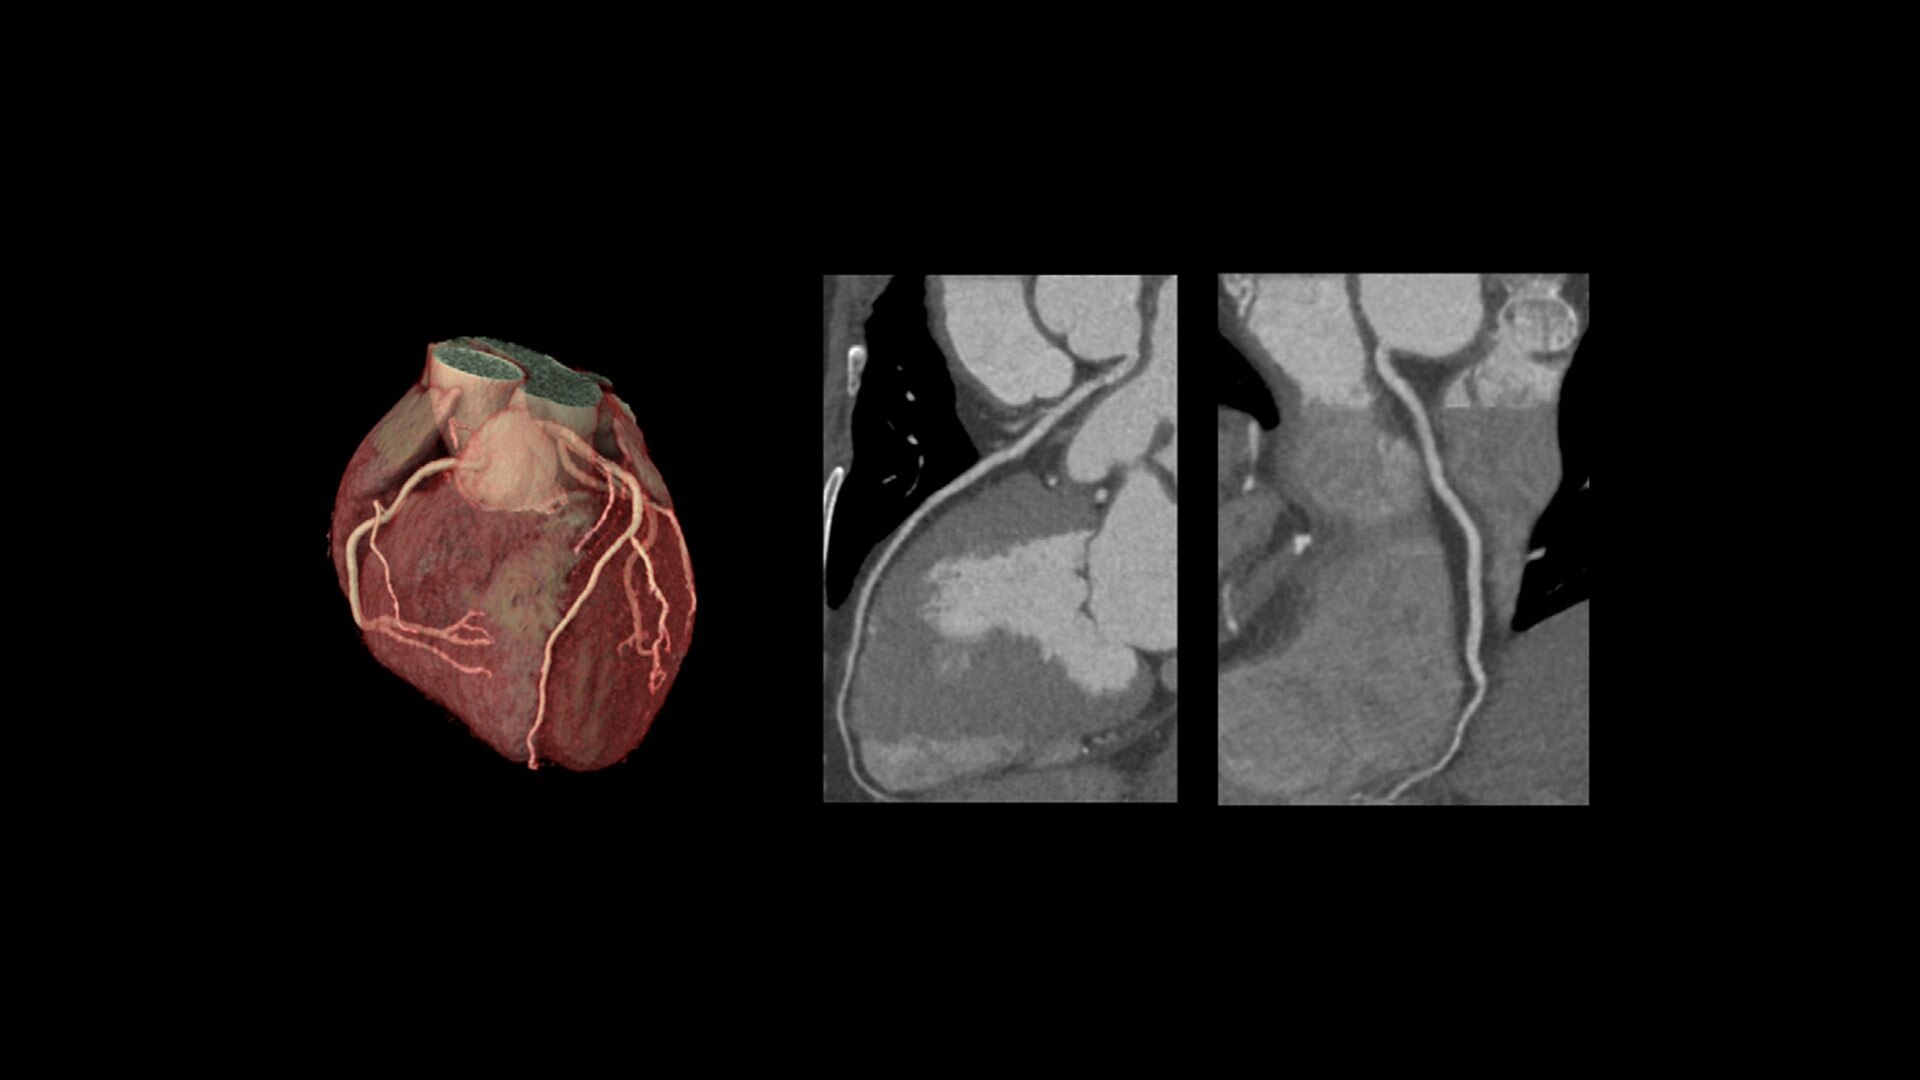

Revolution Ascend Select

High performance for routing and basic coronary analysis

20 mm coverage

32/64 slices

Upgradable to Plus